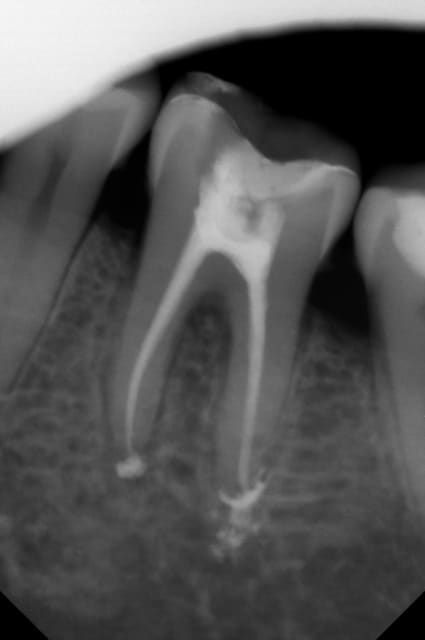

radio de la semaine dernière avant l'endo.

N'y aurait il pas un joli petit dôme de corticale en bonne position dans cette furcation ?

Je la sens moyen au niveau paro pour etre couronnée (furcation...)

J'ai fait un sondage de toute la bouche , et pas de problème relevé au niveau de cette furcation ( pour l'instant)

Elle est très bien ton endo, on s'attend plus à ce résultat sur des dents à l'apex défoncé comme dans les nécroses.

L'obturation sur tuteur fait facilement des dépassements, soigne davantage ta préparation en cône sans exploser le foramen (le dôme d'eugénate) et tu seras parfait.